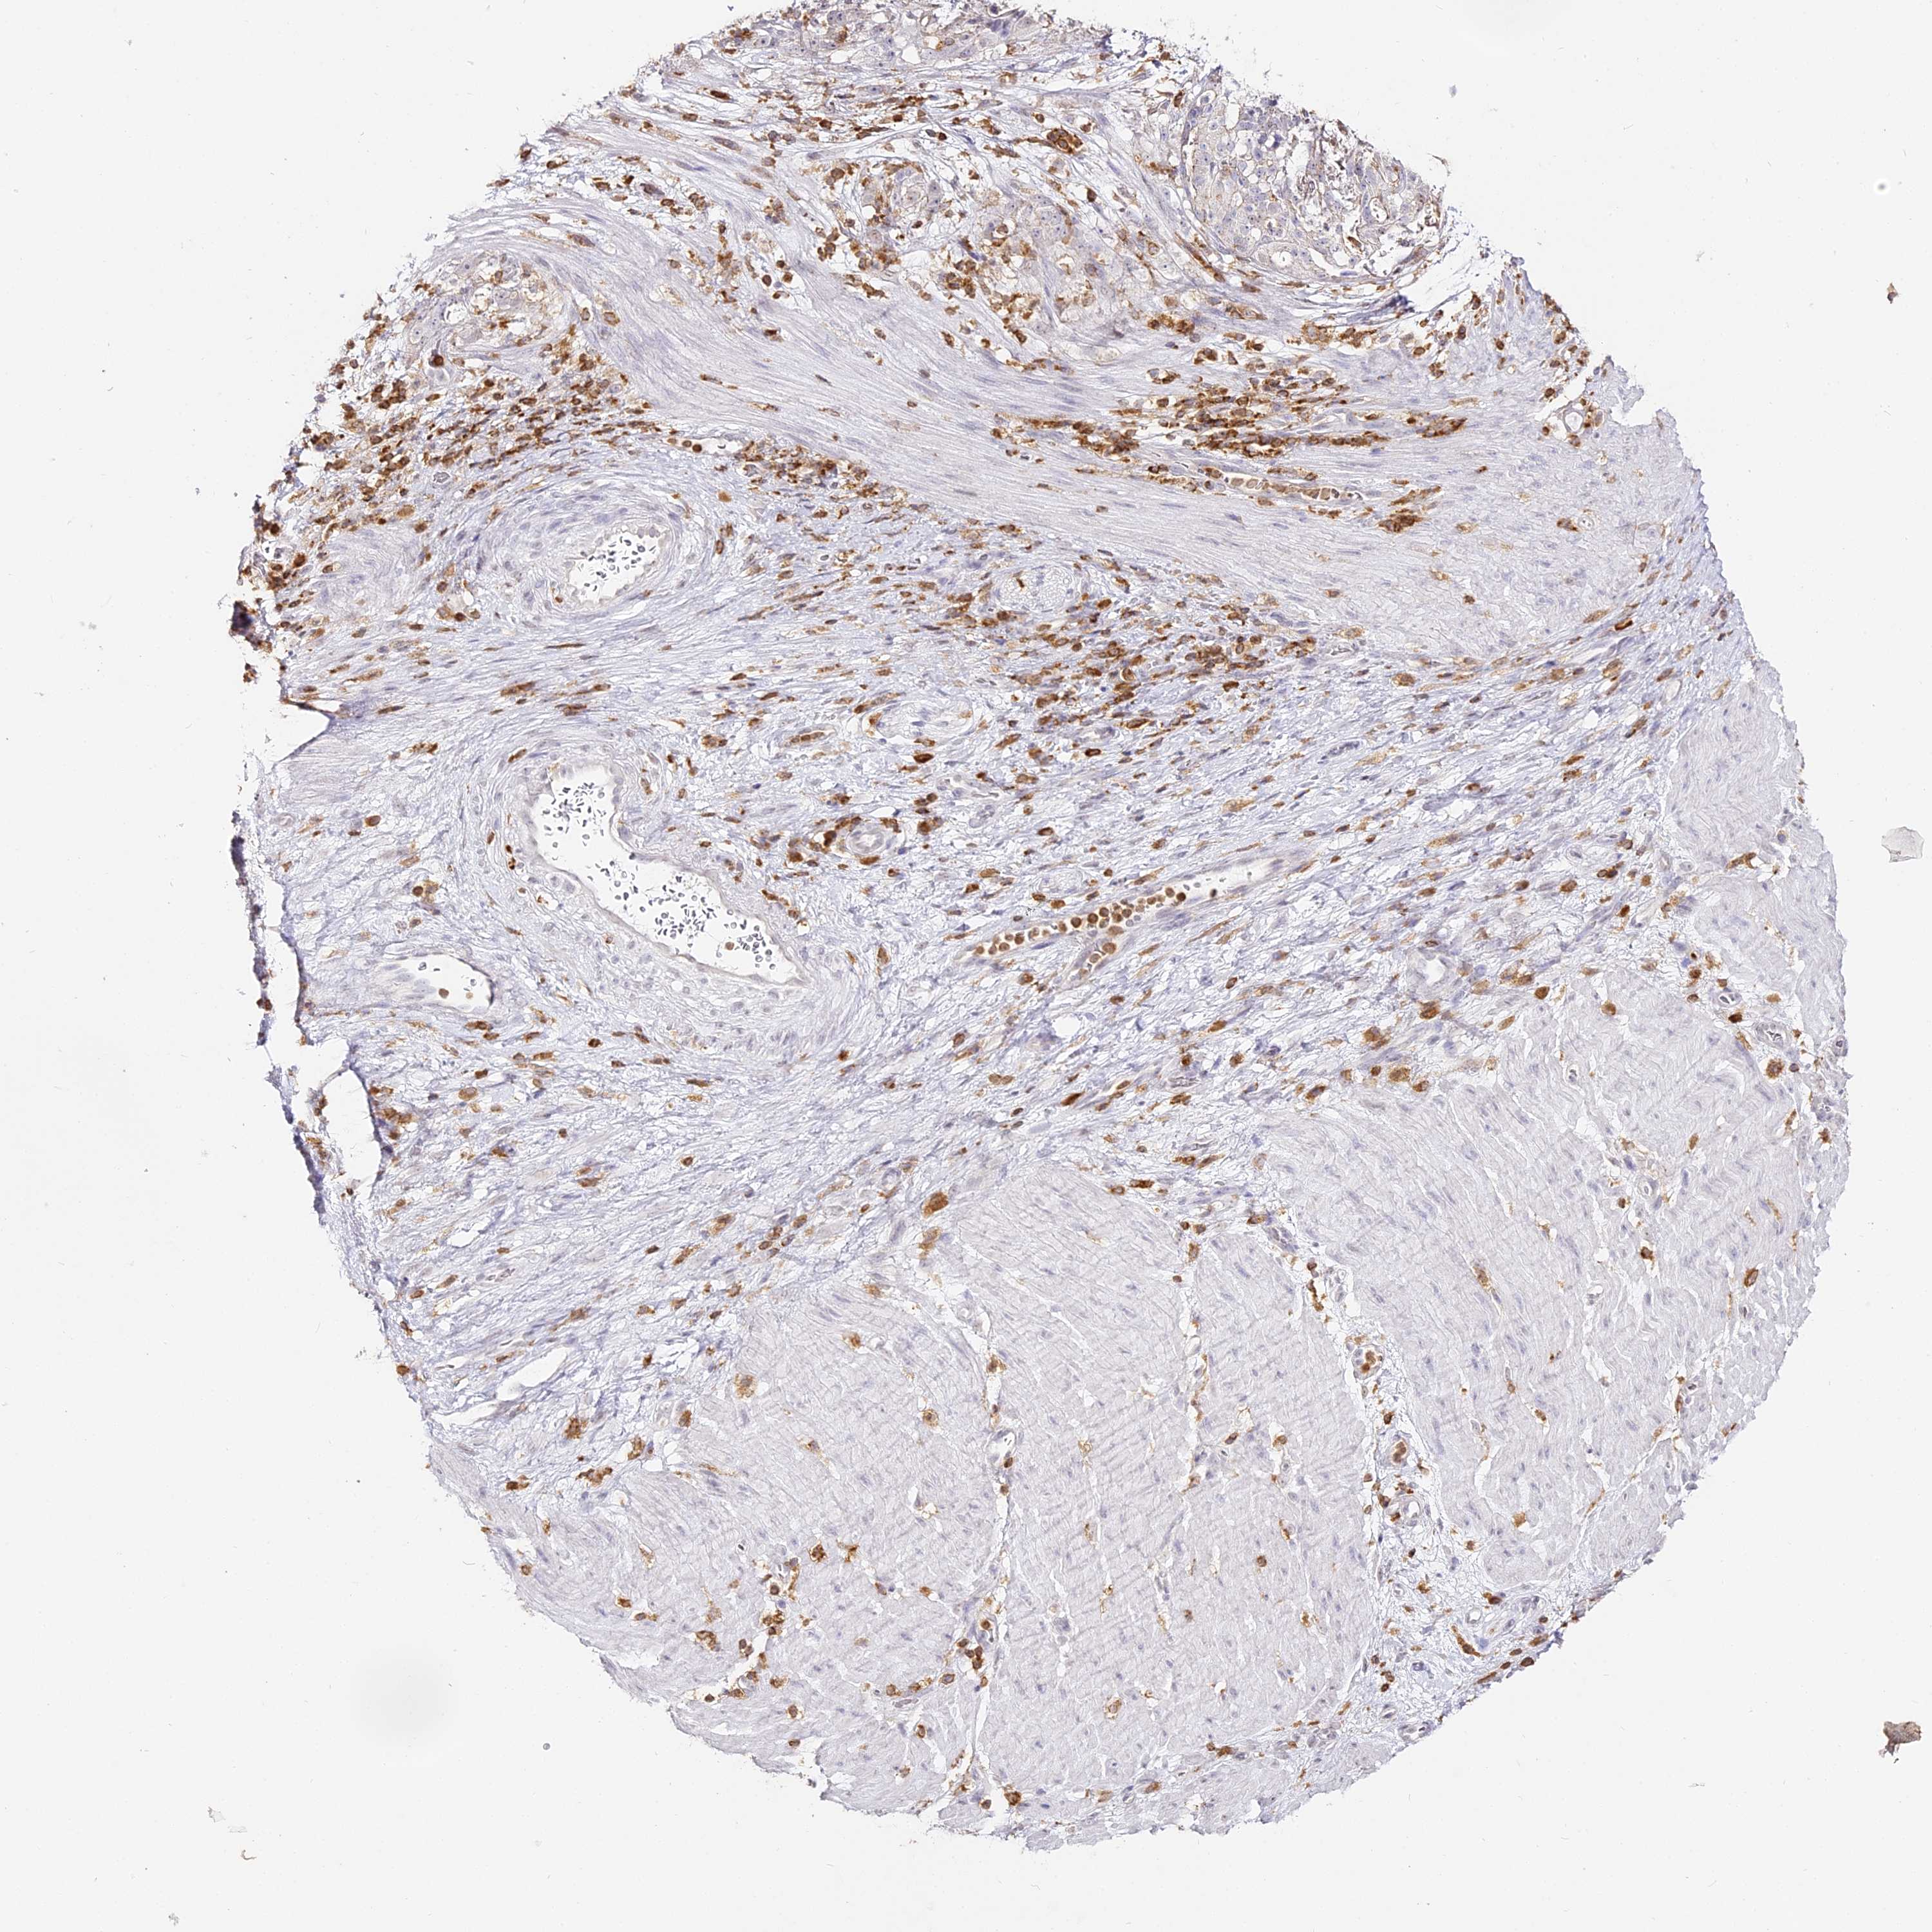

STOMACH CANCER - Protein expressioni

A mouse-over function shows sample information and annotation data. Click on an image to view it in a full screen mode. Samples can be filtered based on level of antibody staining by selecting one or several of the following categories: high, medium, low and not detected. The assay and annotation is described here.

Note that samples used for immunohistochemistry by the Human Protein Atlas do not correspond to samples in the TCGA dataset.

Antibody stainingi

Antibody staining in the annotated cell types in the current human tissue is reported as not detected, low, medium, or high, based on conventional immunohistochemistry profiling in selected tissues. This score is based on the combination of the staining intensity and fraction of stained cells.

Each image is clickable and will lead to virtual microscopy that enables deeper exploration of all samples and also displays staining intensity scores, fraction scores and subcellular localization as well as patient and tissue information for each sample.

Antibody HPA036469

Staining

High

Medium

Low

Not detected

Intensity

Strong

Moderate

Weak

Negative

Quantity

>75%

75%-25%

<25%

None

Location

Nuclear

Cytoplasmic/membranous

Cytoplasmic/membranous,nuclear

Adenocarcinoma, NOS